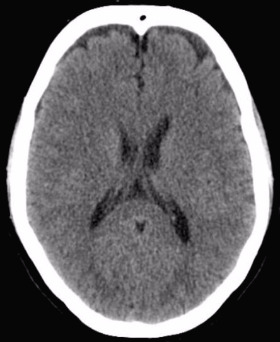

<여기서 잠깐> 뇌경색 혹은 뇌출혈 후에는 뇌부종이 온다. 우리 몸은 정상이 아닌 상황에 대한 염증 반응을 일으키기 때문이다. 우리가 팔다리에 타박상을 입거나, 열상을 입으면 수상 부위가 부어오르는 것과 마찬가지이다. 다음 사진은 정상 뇌와 뇌경색이 발생하여 뇌부종이 생긴 뇌의 CT 사진이다. 좌측의 정상 뇌에 비하여 우측 사진은 뇌경색에 동반된 뇌부종으로(화살표) 뇌가 전반적으로 오른쪽으로 밀려 있는 것을 관찰할 수 있다.

뇌부종이 무서운 이유는 뇌는 단단한 두개골에 싸여 있기에 압력이 밖으로 분산되지 못하고 부어오른 만큼 뇌압을 증가시켜 뇌를 압박하기 때문이다. 이러한 뇌부종은 뇌의 위축이 하나도 없어 두개골 내 공간이 적은 젊은 사람에서 더 위험하다. 본문에서 과장님이 응급수술을 준비하라고 이야기한것 역시 같은 맥락에서 두개골을 제거하여 뇌압을 낮추는 수술이 필요할 가능성이 있기 때문이다.